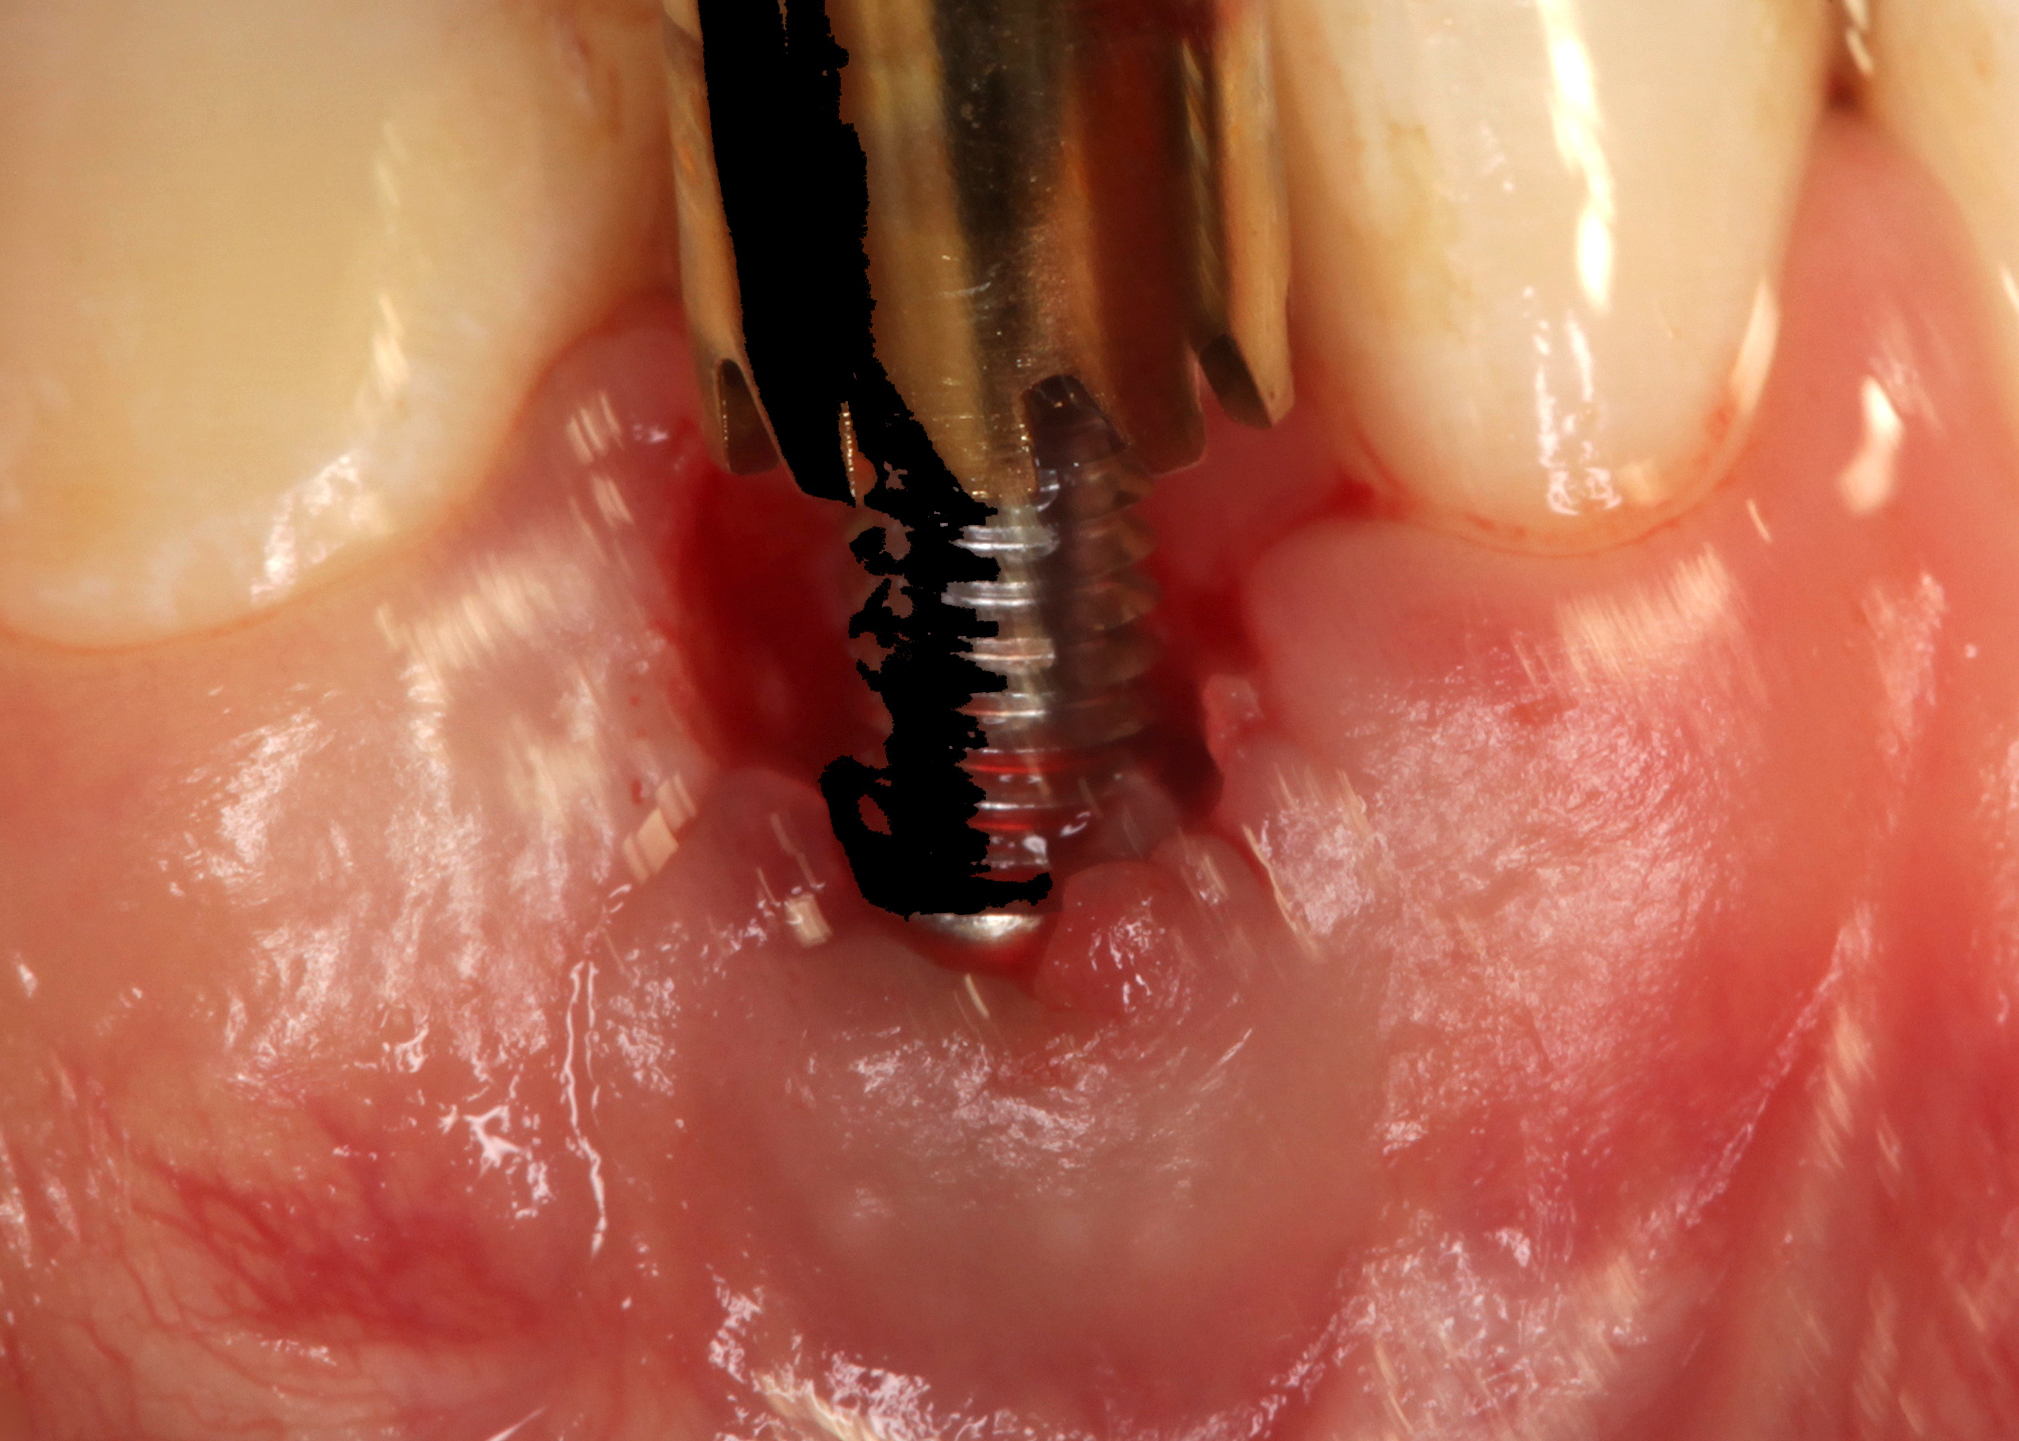

Fig 33. Excessive facial angulation of the implant placement shown with an abutment driver in the access screw hole.

Figure 33

Fig 38. A reverse-torque screw was placed into the implant.

Figure 38

Fig 39. A counter-torque device was placed over the reverse-torque screw.

Figure 39

Fig 40. The implant was easily unscrewed within minutes in a minimally invasive manner with less trauma to the surgical site.

Figure 40